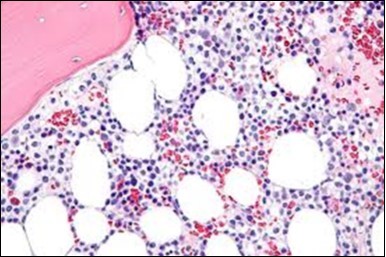

Figure 4.HCL: hairy cells with widely spaced nuclei(20).

The classic hairy cell is medium sized with a magnitude of 10-14µm. The moderately abundant or variable cytoplasm may be transparent or mildly basophilic. The cellular surface with the characteristic serrated perimeter depicts innumerable fragile or stout extensions of cytoplasm ,particularly discernible on the phase contrast and electron microscopy. The cytoplasm may exhibit vacuoles with occasional azurophilic granules4. The nucleus may be elliptical or reniform, folded or indented with a coarse, reticulated or a finely dispersed chromatin and inconspicuous nucleoli along with infrequent mitosis. Bone marrow aspiration or bone marrow trephine biopsy may be inadequate for diagnosis in 30%-50% individuals4. The trephine sections of the bone marrow may depict a characteristic interstitial pattern of leukaemic infiltration. Generally the bone marrow is hyper-cellular, though it may be hypo-cellular in 10-15% individuals4. The leukaemia cell ingress may be diffuse or partial, although diffuse infiltration is frequent. The partial variety of leukaemic dissemination may be ineptly categorized with an indeterminate differentiation from the uninvolved marrow. The malignant insertions may initially emerge as miniature, undefined, cellular loci. The formalin fixed, paraffin embedded sections may elucidate a crystalline zone or a “halo” appearance of the cells with a circumscribed nucleus on account of the plentiful cytoplasm4. The cellular margins may be intertwined. Fixation of bone marrow smears with Zenker’s fixative may demonstrate a retracted cytoplasm of the hairy cells with a consequent disconnected structure. The bone marrow in the absence of a malignant process may be hypo-cellular or hyper-cellular. Reticulin stains may delineate an enhanced accrual of broad, dense reticulum fibres surrounding the aggregates of leukaemia cells with the fibrous circumlocution of individual malignant cell and fibrotic extensions into the abutting, uninvolved bone marrow4.

The leukaemia cells may enunciate a characteristic immune phenotype, crucial for a confirmatory diagnosis. The peripheral blood mononuclear B cell population may display a kappa or lambda light chain restriction. The phenotype of classic hairy cell leukaemia may be delineated by concurrent, immune reactive CD19+ CD20+,CD 11c+, CD25+, CD103+ and CD123+. An intensely immune reactive CD200+ and a non reactive CD27- antigen may be present2, 4. Evaluation of a trephine bone marrow biopsy and bone marrow aspirate may define the degree of tumour infiltration. A dry tap on account of prominent bone marrow fibrosis may be elucidated at preliminary diagnosis. A decline in the normal haematopoiesis may account for a hypo-cellular marrow in 10% instances. Gradation of cellular infiltrating of the leukaemia within the bone marrow may be appropriately investigated with immune –histochemical stains2, 4. Immune staining for CD20+, annexin 1 and VE1 (a BRAF V600E stain] may validate the diagnosis and precisely analyse the extent of malignant bone marrow infiltration[8]. Determination of BRAF V600E mutation may be critical in therapeutically non responsive individuals with applicable standard therapy or in instances of multitudinous reoccurrences[9]. Deploying inhibitors of BRAF V600E gene may be efficacious in patients impervious to approved therapy. The mutation necessitates a comprehensive scrutiny of the implicated individuals with a sensitive molecular assay which may discern up to < 10% of the hairy leukaemia cells appearing in the peripheral blood smears or bone marrow aspirates diluted with peripheral blood or aspirates elucidating a dry tap[2,4]. Allele specific polymerase chain reaction (PCR) or a next generation sequencing may be optimally employed to circumvent false negative outcomes. If the leukaemia cells are sparse or if particularly sensitive & efficacious molecular techniques are not accessible, the application of appropriate immune histochemical stains to the bone marrow biopsy such as a BRAF V600E mutation stain (VE1) may detect the hairy cells and conclusively diagnose the condition[2,4,10]. Figure 1, Figure 2, Figure 3, Figure 4, Figure 5, Figure 6, Figure 7, Figure 8, Figure 9, Figure 10, Figure 11, Figure 12, Figure 13, Figure 14.